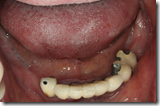

患者A先生

上顎 正面 下顎

患者B小姐

以上兩位患者口內狀況非常複雜,要制定一個好的治療計畫,

不只要考慮到患者的牙齒條件,